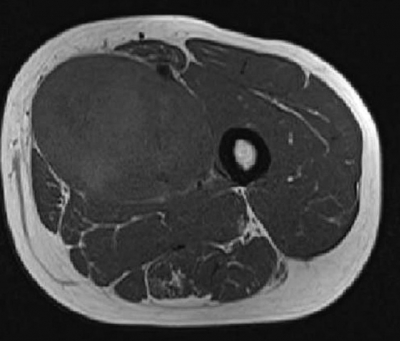

意識は清明。身長 172 cm、体重 78 kg。 体温 36.3 ℃。脈拍 72/分、整。血圧 126/78 mmHg。胸腹部に異常を認めない。左大腿近位内側に弾性硬の腫瘤を触知するが、発赤、腫脹および圧痛はない。皮膚との可動性は良好だが、深部との可動性は不良である。血液生化学所見に異常を認め ない。左大腿近位 MRI の T1 強調像と T2 強調像とを示す。

最も可能性が高いのはどれか。

d. 悪性軟部腫瘍